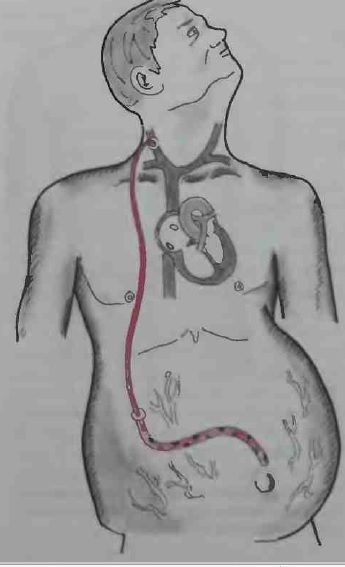

Вентрикуло-перитонеальный шунт: Показания и применение

Раздел: Фотоальбом решений